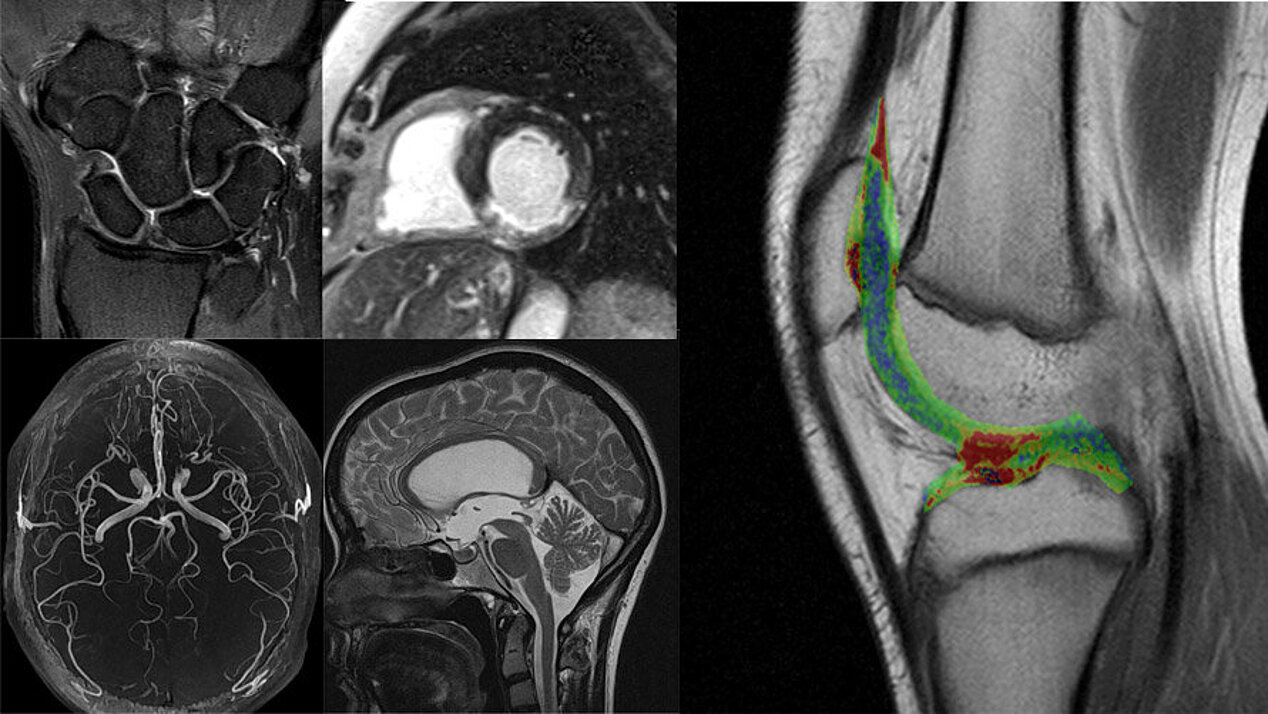

Diagnostik im offenen MRT

- Kopf

- Wirbelsäule

- Gelenke, Sehnen & Muskulatur

- Hals, Brust- & Bauchraum

- Beckenorgane

- Mamma-MRT & Prostata-MRT nur bei Platzangstpatienten